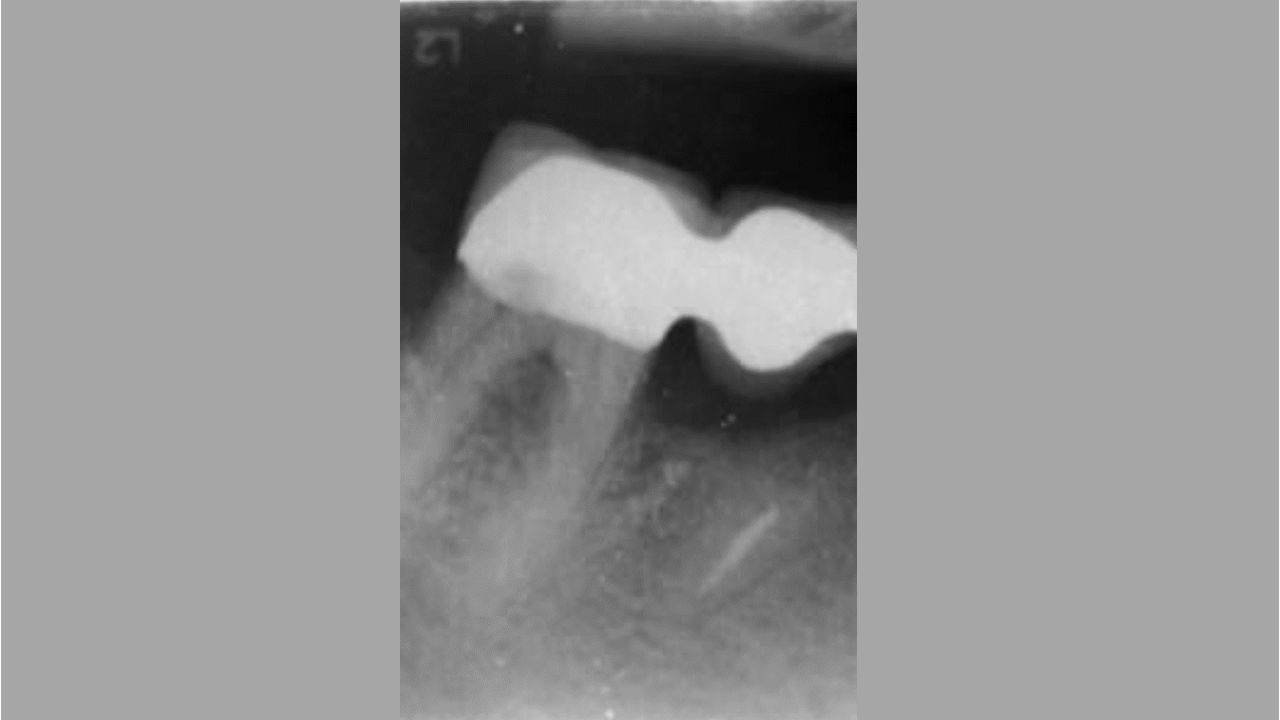

01/06 - Pre-operative radiographic view.Intrabony defect treated using Straumann® Emdogain®, cerabone® and Jason® membrane - Dr. D. B. Hangyási